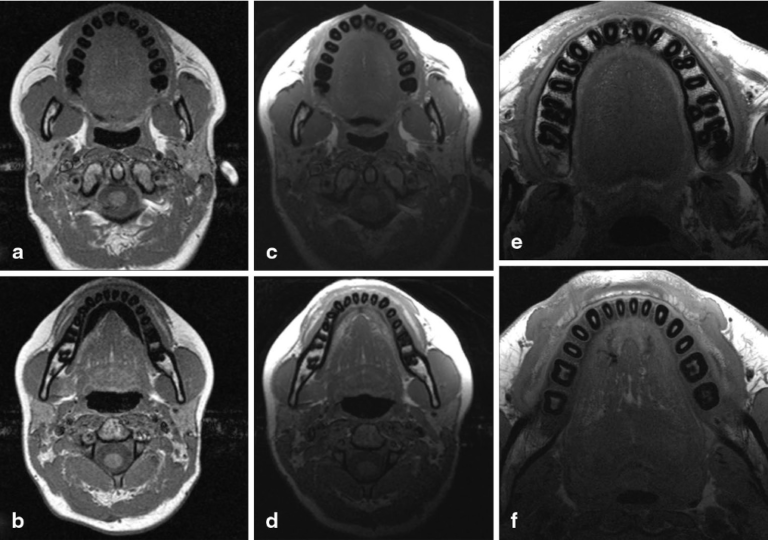

Can You Do An Mri With Dental Implants. Having an mri scan with dental implants is safe. undergoing an mri (magnetic resonance imaging) scan can raise concerns for patients with dental implants. However, it is essential to communicate with your healthcare provider regarding your dental implants before the scan. Before your mri, it’s important to inform the technician about your implants, so they can take any necessary precautions. Fortunately, modern dental implants are designed with materials that minimize the above risks. Most dental implants are made from materials that are safe for mri scans. Dental implants are typically made of materials that are not affected by the magnetic. is it safe to get an mri scan with dental implants? but can you get an mri with dental implants? the good news is that you can indeed undergo an mri scan with dental implants. yes, you can have an mri with dental implants. Fortunately, in most cases, modern dental implants and mris are a safe combination. experts agree that, as long as you don’t have ferromagnetic dental implants, an mri is generally safe. Mri machines generate powerful magnetic fields that could potentially induce movement or heating of the implants. yes, it is possible to have an mri with a dental implant.